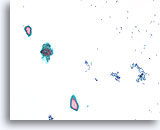

Afbeelding 19

Cellaesie, folliculair neoplasma (lymfocytische thyroïditis vs hurthlecelneoplasma) kan niet worden uitgesloten, schildklier FNA, ThinPrep®.

De hurthlecellen hebben een microfolliculaire organisatie. Er zijn een paar lymfocyten door het epitheel gemengd, hetgeen pleit voor lymfocytische thyroïditis.

60X

Afbeelding 19

Cellaesie, folliculair neoplasma (lymfocytische thyroïditis vs hurthlecelneoplasma) kan niet worden uitgesloten, schildklier FNA, ThinPrep®.

De hurthlecellen hebben een microfolliculaire organisatie. Er zijn een paar lymfocyten door het epitheel gemengd, hetgeen pleit voor lymfocytische thyroïditis.

60X